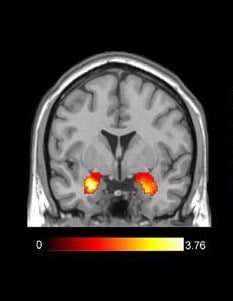

Amygdala activation

A standard fMRI image. The highlighted area shows the activation of the amygdala. (Photo Credit : G.KONSTANTINA/Wikimedia commons)

When an area of the brain is activated, there is a rush of blood to that area. The fMRI captures this change in blood flow. It helps scientists understand which activities light up what parts of the brain. Understanding which brain area activates in response to certain stimuli enables scientists to understand human behavior. Using fMRI, the researchers observed which parts of the brain were activated when the different drinks were consumed.